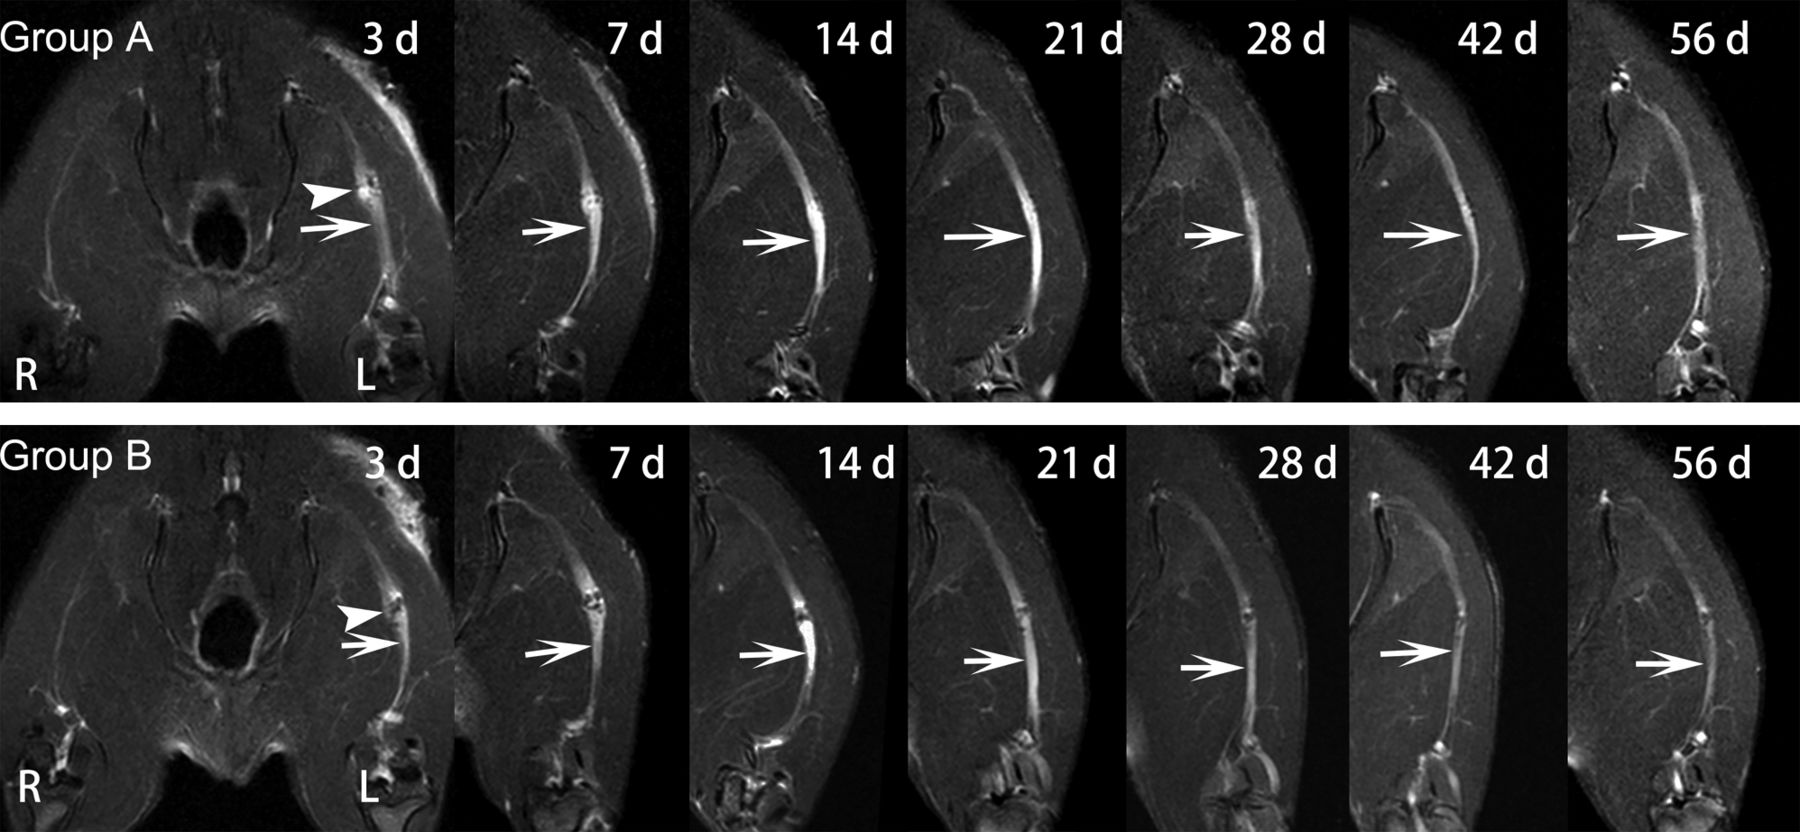

In groups A and B, obvious nerve enlargement, and substantial gadofluorine enhancement and signal abnormality were observed in the distal stumps 3 days after surgery, followed by gradual decrease during the 8-week follow-up. T2 signal abnormality and nerve enlargement returned to almost normal at 6 weeks after surgery in group A, whereas it was at 8 weeks after surgery in group B (Fig 1). Gadofluorine enhancement in groups A and B slowly declined but persisted until 8 weeks after surgery in the distal stumps of nerve. Gadofluorine enhancement was more prominent in the distal stumps of nerves in group A than in group B during the entire study period (Fig 2).

Sequential fat-suppressed T2-weighted images of injured nerves repaired with epineural coaptation. Nerves in group A (LPS treatment) and group B (PBS treatment) show obvious signal abnormalities in the lesion site (arrowhead) and distal stumps (arrows), which gradually declined over time. R = right hind limb; L = left hind limb.

Sequential gadofluorine-enhanced fat-suppressed T1-weighted images of injured nerve repaired with epineural coaptation. Persistent enhancement appears in the lesion site (arrowhead) and distal stumps (arrows) in group A (LPS treatment) and group B (PBS treatment). R = right hind limb; L = left hind limb.